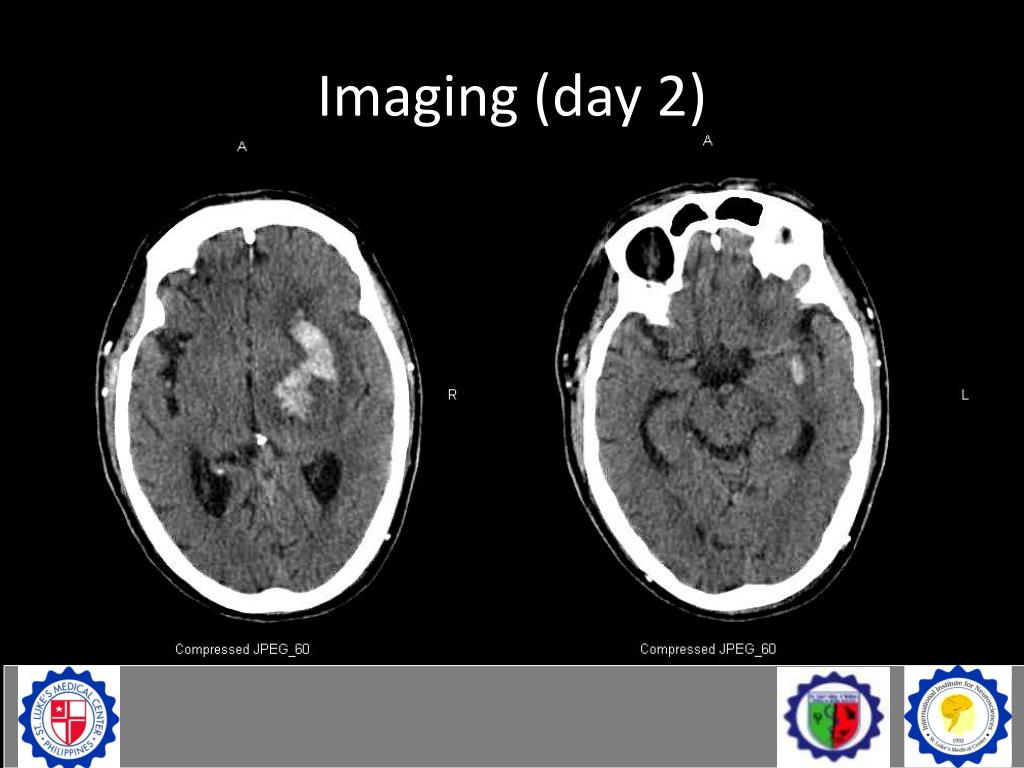

19. Imaging (day 2)

20. Imaging (day 2)

21. Imaging (day 2)

22. Imaging (day 2) • Interval evolution to beginning subacute stage • Without increase in volume • Interval progression of perilesional edema • Midline shift to the right has not significantly changed